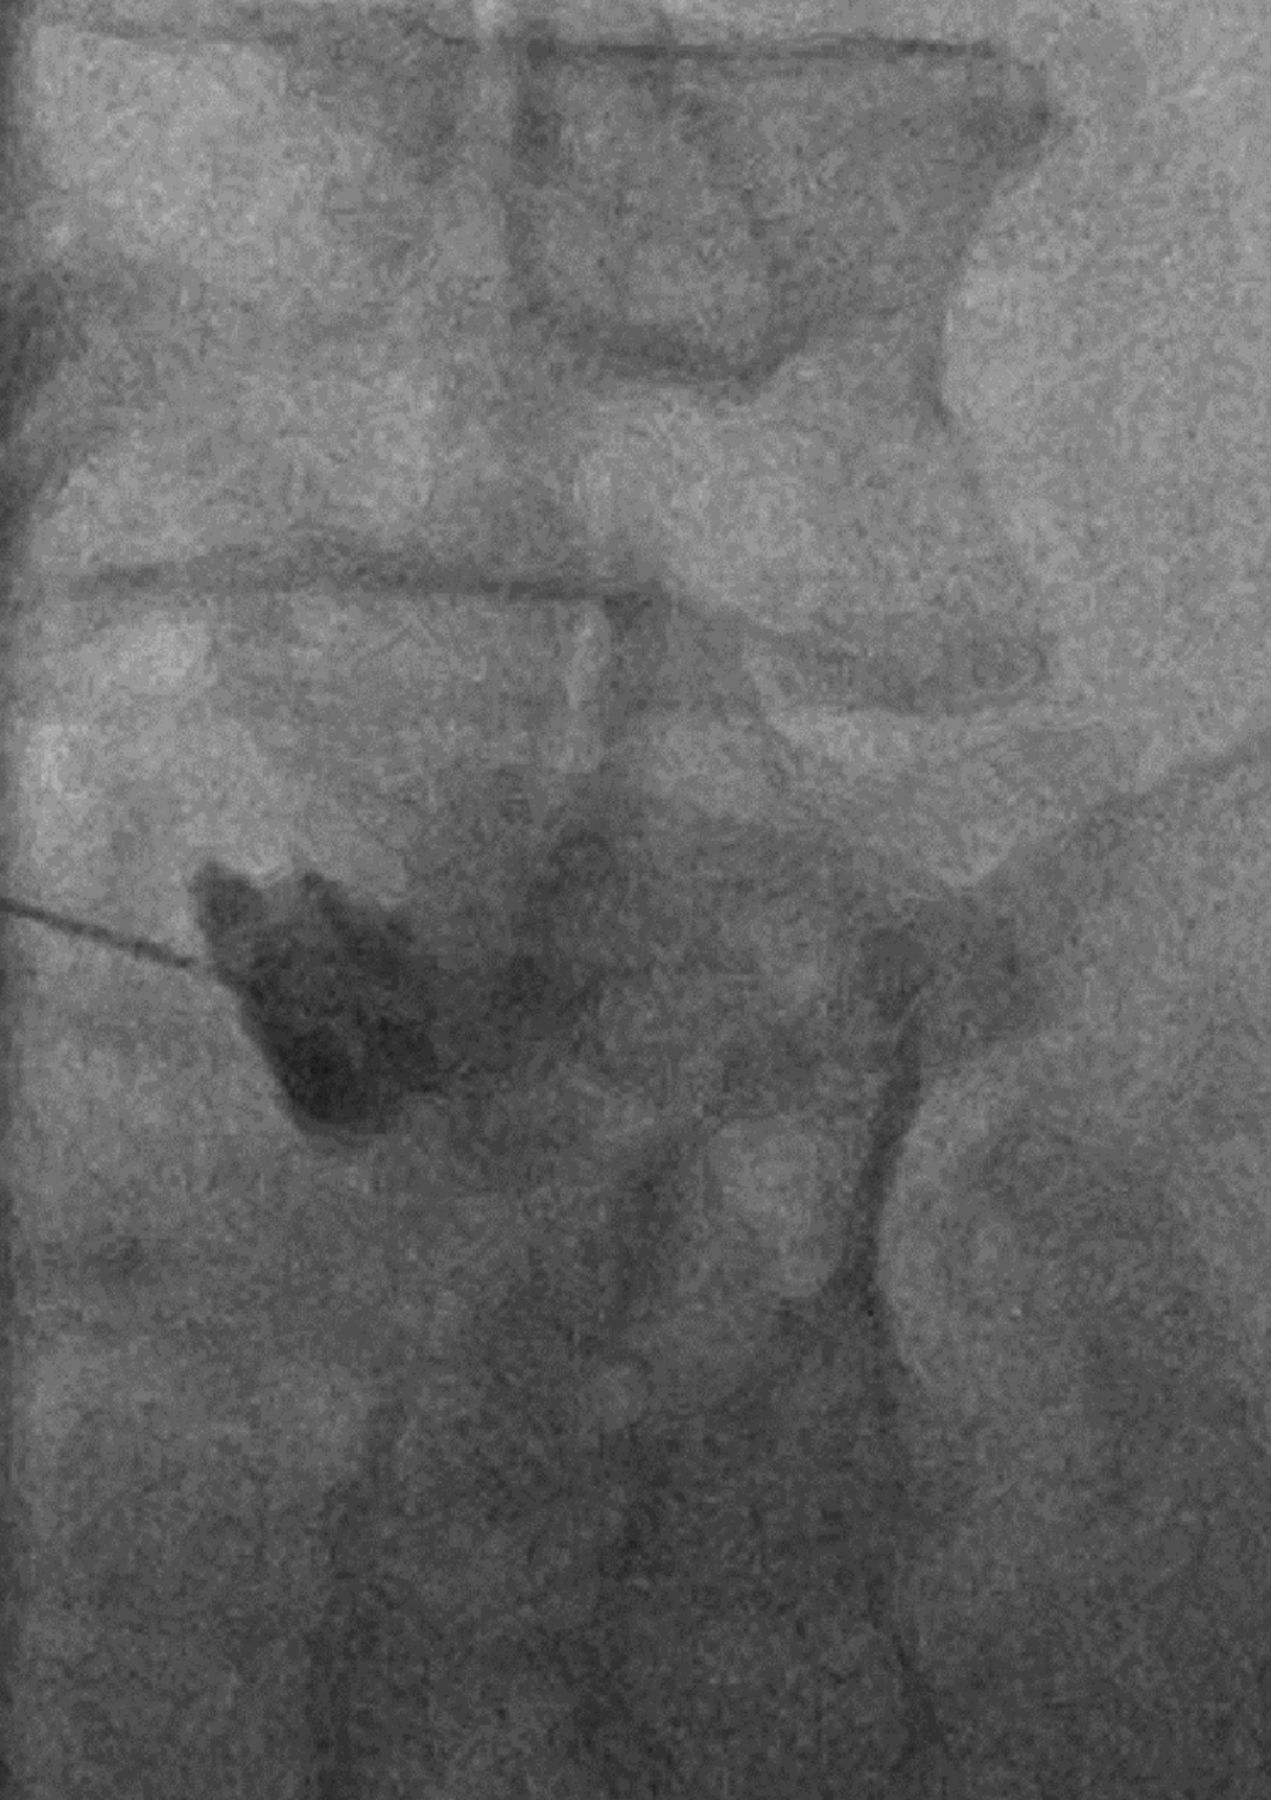

Oblique fluoroscopic image of the L4–L5 facet joint demonstrates a periarticular injection. Contrast pools around the needle tip adjacent to the hypertrophied facet joint. No contrast is identified within the joint or joint recess.